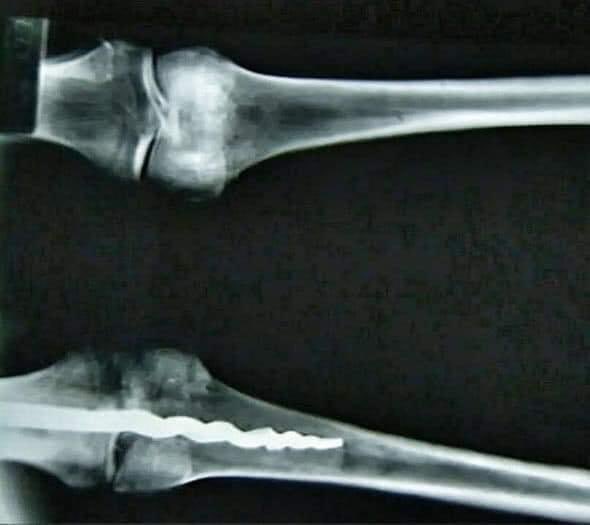

" العلماء في ٢٠١٥ اثناء فحصهم الروتيني لمومياء مصرية قديمة خمسينية تعود الي الدولة الحديثة عمرها ٣٥٠٠ سنة اكتشفوا تكوين غريب للركبة اليمنى للمومياء فراحوا عاملين فحص كامل للقدم ووجدوا جسم معدني غريب مزروع داخل الركبة عبارة عن حاجة شبه

المسمار طولها حوالي ٢٣ سم ومُثبت بصمغ عضوي داخل عظام وانسجة الركبة الموضوع كان مفاجأة كبيرة ليهم لما عرفوا فايدة المسمار ده وهو انه كان نتاج عملية شديدة التعقيد لتقويم عظام الركبة ودي حاجة العلم الحديث مقدرش يعرفها غير بعد ٣٥٠٠ سنة

الموضوع من كتر ماهو لا يصدق طلبوا رأي احد كبار الاطباء وهو الدكتور "ريتشارد جاكسون" رئيس قسم جراحة العظام في جامعة بريغام اللي بدوره فحص الركبة وبعدها قال مستحيل حد قبل ٣٥٠٠ سنة يقدر يعمل عملية بالبراعة دي خاصة انه شاف تصميم المسمار والدعامات اللي حواليه واللي قال عنها انها مش

بس جراحة متطورة لا وكمان وشبيهة بالمُستخدمة في جراحة الركبة الحديثة الآن من حيث تقنية استقرار ثقل الجسم على الركبة وفي نهاية الجلسة طلع في مؤتمر صحفي وقال " يبدو ان هناك الكثير من الاسرار في علم المصريات لم تكتشف بعد وانه لو تم هذا الاكتشاف قبل ١٠٠ سنة فقط